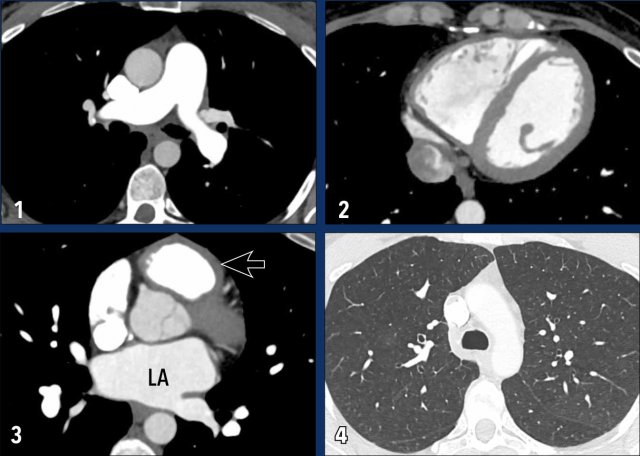

These images are of a patient with pulmonary hypertension secondary to partial anomalous pulmonary venous return (PAPVR).

Imaging Findings

The right lower lobe pulmonary veins are not connected to the left atrium (LA) but instead drain into the superior vena cava (arrows).

Note the bilateral dilatation of the pulmonary arteries, consistent with elevated pulmonary arterial pressure.

Atrial Septal Defect (ASD)

In an Atrial Septal Defect (ASD), there is a communication between the left and right atrium.

Since left atrial pressure is higher, blood flows from the left atrium to the right atrium.

This increases blood volume in the right heart and pulmonary circulation.

The chronically elevated flow and pressure in the lung circulation causes endothelial damage, vascular remodelling and an increased pulmonary vascular resistance.

Illustration

Example of a sinus venosus superior defect.

This is a subtype of ASD, in which there is an abnormal interatrial communication between the left atrium and the superior cavo-atrial junction (arrow).

Since this subtype of ASD frequently coexists with PAPVR, always check for both conditions.

Images

1. There is an abnormal communication between the left atrium and the superior cavo-atrial junction (arrow).

2.  Dilatation of the pulmonary artery.

3. Coronal reconstruction demonstrating the abnormal communication between the left atrium and the superior cavo-atrial junction (arrowheads).

4. Severe dilatation of the right atrium and ventricle due to the left-to-right shunt.